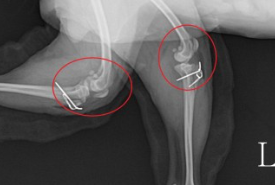

슬개골 탈구는 진행 정도에 따라 1기부터 4기까지 나뉘며, 1기는 가벼운 탈구로 슬개골이 자연적으로 제자리로 돌아가고, 4기는 심한 탈구로 슬개골이 제자리로 돌아가지 않고 통증이 심해집니다. 슬개골 탈구의 진단은 병원에서 촉진 검사나 X-선 검사를 통해 할 수 있습니다.

슬개골 탈구의 치료 방법은 단계와 상태에 따라 다르지만, 일반적으로 2기 이상이면 수술을 권장합니다. 수술은 슬개골을 제자리에 고정하거나 활차구를 깊게 만들어주는 방법 등이 있습니다. 수술 후에는 꾸준한 관리와 재활이 필요하며, 관절 보조제나 치료식을 급여하는 것도 도움이 됩니다.